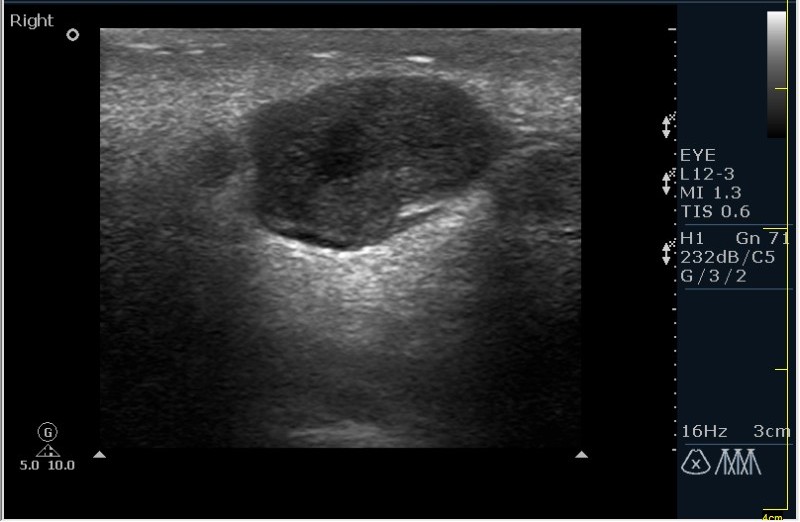

Мужчина 68 лет, направлен на УЗИ правой слюнной железы. Жалобы на пальпируемое, малоболезненное плотное образование за правым ухом.

Марио, что при компрессии образования -"зыбается" ли? т.е. образование солидное или жидкостное?

Солидное!!!! Я тоже ТАБ хотел сделать, но ЛОР заказал КТ... А какие мысли будут?

Первая мысль о очаговом воспалении, деструктивной фазе, но нет клиники.

Тумор?

Клиники нет, тумор на первом месте. В принципе КТ (или МРТ) заказывают для диффиренцировки зло/добро. Плюс посмотреть есть ли локальное растпространение. Но в данном случае я думаю УЗИ с ТАБ было бы достаточно.

Согласен! Поэтому в КТ отказал и настоял на ТАБ. Итак? Варианты?